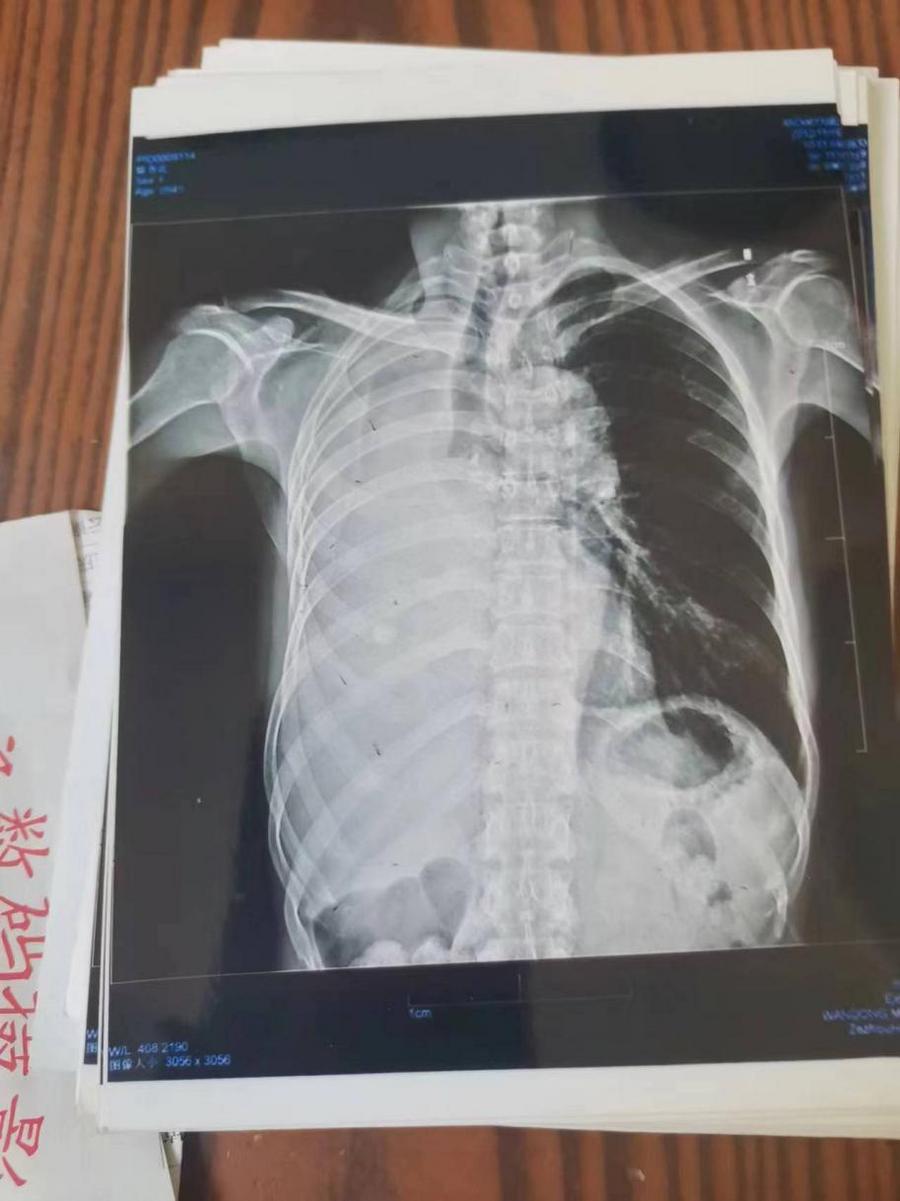

案例4右肺上叶癌(左侧颈部淋巴结转移、鳞状细胞癌)

患者岂六荣,53岁,系山西省晋中市左权县石匣乡管头村,于2013年1月9日前来就诊。因左胸憋闷,右肺呼吸困难,后背呈放射性疼痛近日加重。于2012年8月7日就诊于山西医科大学第一附属医院,行胸部CT示:右肺上叶癌,行气管镜示;右上叶后段支气管肺癌,右上叶支气管与右中间支气管分膌,右中间支气管开嗳累,病理回报:鳞状细胞癌(病理号12-12929)。于8月30日就诊于山西省肿瘤医院接受治疗。经该院各项检查最后诊断:右上叶癌: 左侧颈部淋巴结转移,鳞状细胞癌,化疗后出院于2012年9月19日转山西武警总医院(第一次入院),2012年9月19日。住院期间经过完善的相关检查,期间出现血小板低下,给予升血小板治疗后,血小板恢复正常,后行伽玛刀治疗后,同时给予中药抗肿瘤药今患者及家属要求出院,于2012年10月10日家属要求出院,住院21天。出院诊断;1、右肺上叶癌2、左侧颈部淋巴结转移3、血小板低下,白细胞低下4、乙型肝类(恢复期)。第二次住院(2012年11月9日)出院(2012年11月21日)共住院12天。今患者及家属要求出院,于今日自动出院。

The patient, Hui Liurong, 53 years old, from Guantou Village, Shixia Township, Zuoquan County, Jinzhong City, Shanxi Province, came for medical treatment before January 9,2013. Due to the stuffy left chest, the right lung had difficulty in breathing, and the back radiation pain was recently aggravated. On August 7,2012, she presented to the First Affiliated Hospital of Shanxi Medical University, with chest CT: right upper lung carcinoma, tracheoscopy; right upper posterior bronchopulmonary carcinoma, right upper bronchus and right middle bronchus, right middle bronchial opening, pathological return: squamous cell carcinoma (pathology no. 12-12929). On August 30, he was treated at Shanxi Cancer Hospital for treatment. In the hospital, he was diagnosed: left cervical lymph node metastasis, squamous cell carcinoma, discharged after chemotherapy, he was transferred to Shanxi Armed Police General Hospital on September 19,2012 (admission for the first time), on September 19,2012. During the hospitalization, platelet deficiency occurred during the period. After treatment with ascending platelets, the platelet returned to normal. After gamma knife treatment, the patient and his family members were required to be discharged. On October 10,2012, the family members required to be discharged and hospitalized for 21 days. Discharge diagnosis; 1. Cancer of right upper lung 2, left cervical lymph node metastasis 3, low platelet, low white leukocyte 4, type B liver (recovery period). The second hospitalization (9 November 2012) and discharge (21 November 2012) lasted 12 days. The patient and his family request to be discharged today, and he will be discharged automatically today.

于2o13年1月8日一2o13年5月28日纯中药临床治愈,14o天清零。停药一年半后做医学鉴定:未见肿瘤细胞。至今11年未見复发,未見转移,不服药。一直从事农业劳动。于2024年2月10日(春节)上午10点接通岂六荣电话时,他正赶着羊群往后山上的路上,当我问到中午吃饭怎样解决时:因后山上离村有六七里山路,只有随干粮充饥,并告诉我每天上午10点准时出犮,下午4点半就回到家了。当我问到他身体时:"自从在您那里治好后十一年至今天,不复发,不服药。我很好,很健康,请陈大夫放心”。今天是过大年,你们早点回去,给您拜年,祝您全家新年快乐,平安,幸福!

On January 8,2o13, May 28,2o13, pure Chinese medicine was clinically cured, and cleared in 14o days. A year and a half after the medical identification: no tumor cells. There is no recurrence, no metastasis in 11 years, and no medication. Has been engaged in agricultural labor. On February 10,2024 (Spring Festival), at 10 am on the phone, he was driving the sheep on the mountain, when I asked how to solve the lunch: because there are six or seven li mountain road from the village after the mountain, only to satisfy the dry food, and told me to go out at 10 am every day, and returned home at 4:30 in the afternoon. When I asked him about his body, " Eleven years since your cure to today, no relapse, no medication. I am very good, very healthy, please rest assured that Dr. Chen."Today is the New Year, you go back early, give you a New Year, I wish you and your family a happy New Year, peace and happiness!

岂六荣的癌症通过陈老师的高超技艺彻底治愈,前几天陈老师跟他通话他还在山上放羊,山上的温度很低大约在零下二十多度,在山上放羊,追逐羊群,没有好的身体根本不行。现在岂六荣的身体状态特别好,甚至比之前的身体还好。这就是中医药的魅力所在,伟大之处。

A few days ago, he was still herding sheep on the mountain. The temperature on the mountain was about 20 degrees below zero. Now the six rong's physical condition is particularly good, even better than the body before. This is where the charm and greatness of traditional Chinese medicine.